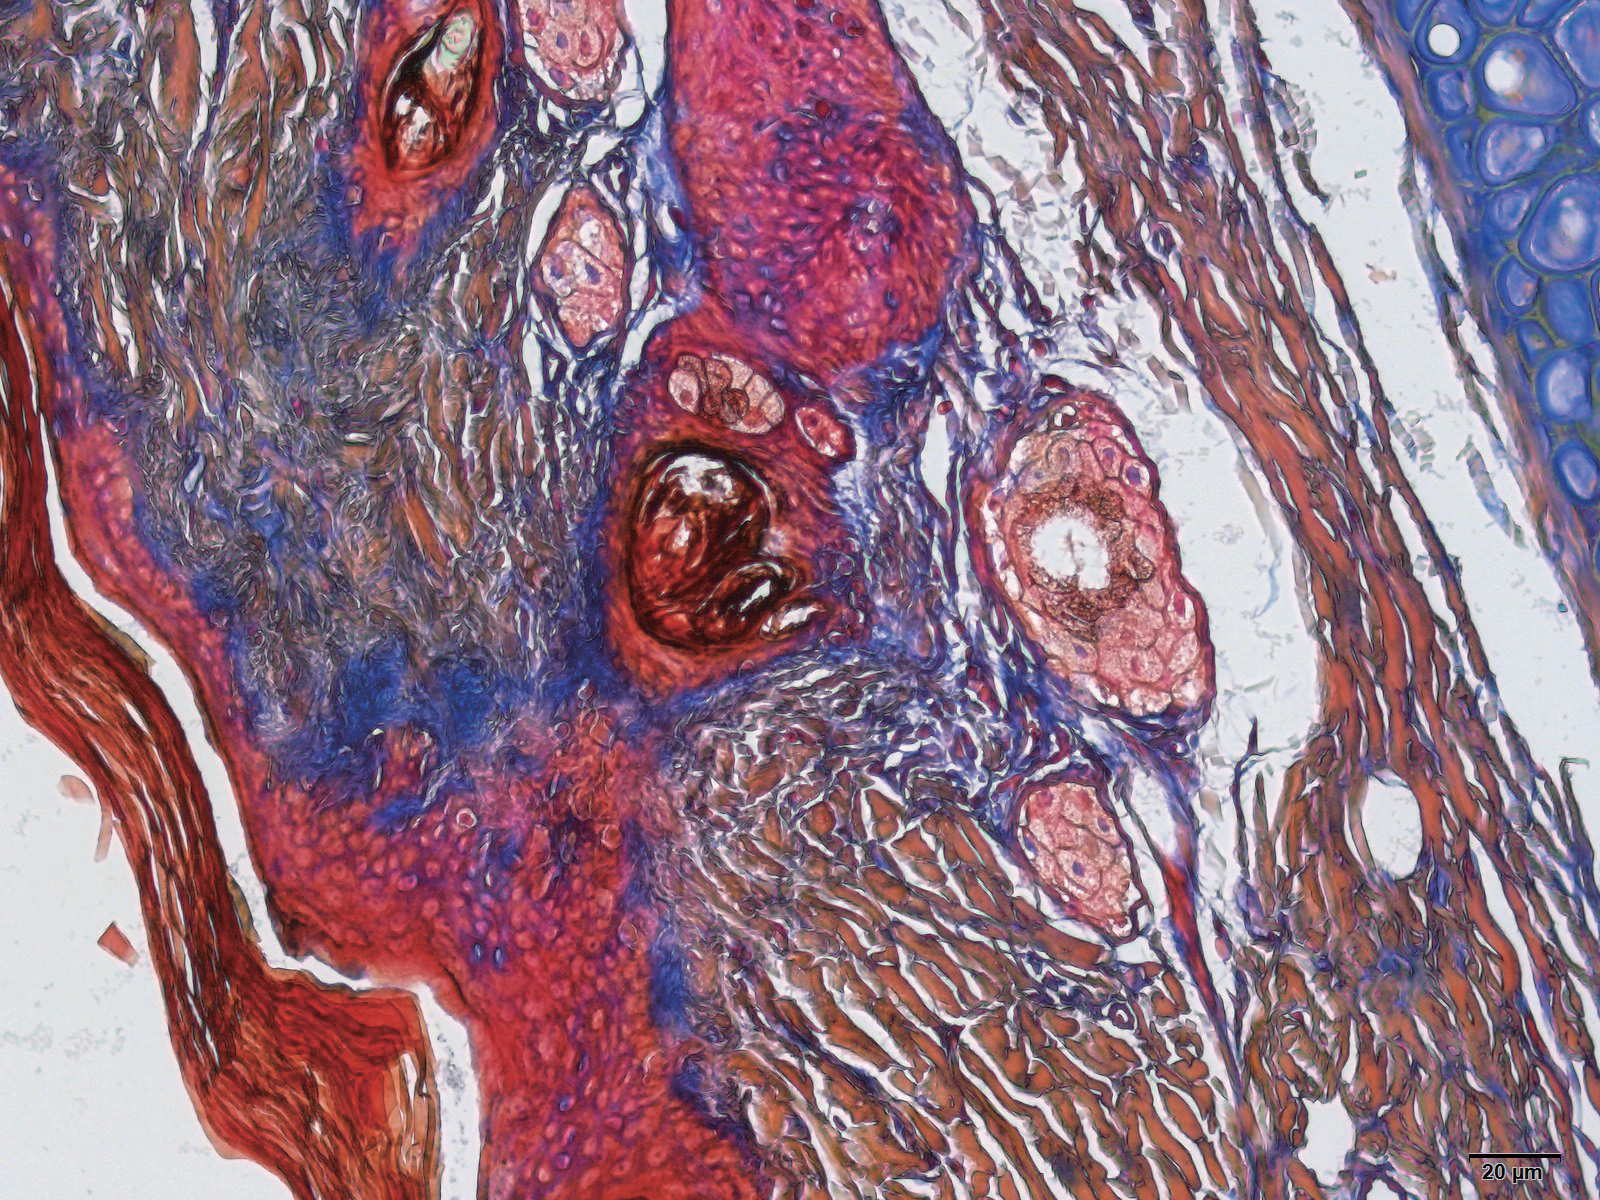

天狼星染色vs股骨病理分析

尼氏染色VSMallory染色